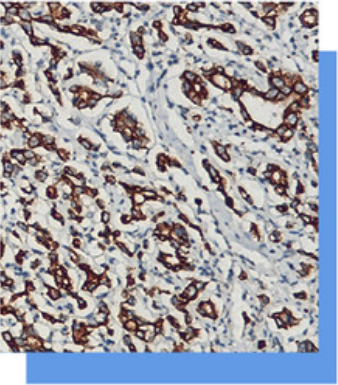

CD31抗体试剂

细胞角蛋白(广谱)抗体试剂(免疫组织化学)

CK Pan在正常的各种.上皮细胞中染色阳性。其主

要应用于.上皮源性肿瘤的诊断以及鉴别诊断,是常用

免疫表达广谱的一种抗体。另外在类癌、小细胞癌、

移行细胞癌、混合癌、室管膜癌、胸腺癌、脊索癌、

间皮瘤生殖细胞肿瘤中CK Pan呈阳性。